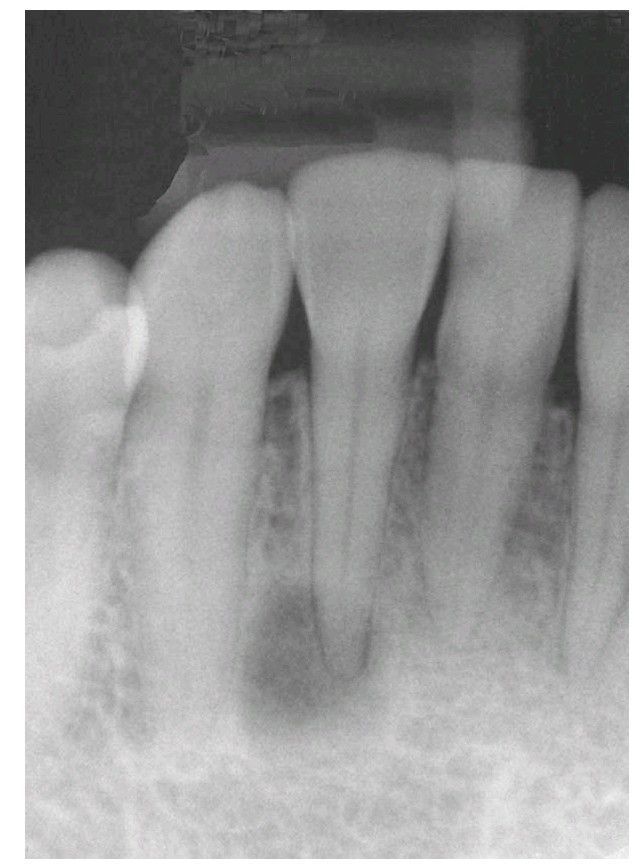

Cementoma

Radiograph of what appears to be a periapical lesion associated with a nonvital tooth; however, the tooth is vital. The appearance of apical bone loss is actually secondary to a cementoma.